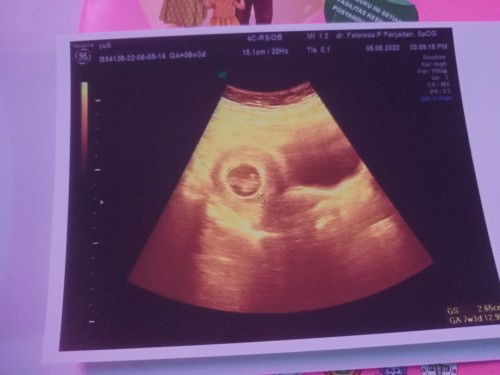

Tanya hasil USG

Mau tanya dong bun, usia kehamilan itu kan yg diatas klo yang dibawah itu apa ya sama2 tulisan nya GA

GA yg atas biasanya input sesuai hpht. GA yg dibawah sesuai ukuran janin. jadi sesuai hpht usia nya 8w, janin nya ukuran 7w. masih batas normal